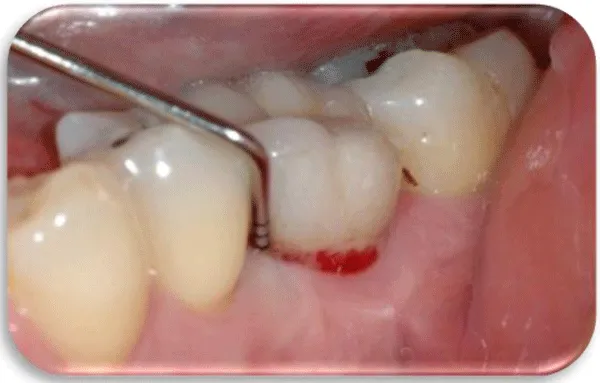

Peri-implant diseases are classified into two categories: - Peri-implant mucositis, which would be described as a bacterial-induced, inflammatory process that involves soft tissue. Clinically, redness of the gingiva is noticeable, it is oedematous and bleeding occurs during the probing.

- Peri-implantitis characterized by progressive, inflammatory destruction of the alveolar bone around the implant. Deepening of the gingival sulcus occurs, the purulent and bloody contents are drained during the projection [10,11] (Figures 2,3).

In peri-implant mucositis, the marginal gingiva in lightly bleeding bleeds. Gingiva is hyperemic and oedematous. The patient feels discomfort, mastication of food also leads to bleeding (Figure 4) [16].

With the progression of the peri-implant mucositis, the soft tissue condition around the dental implant is aggravated. Bone tissue destruction begins inside the alveolar bone around the implant itself, causing bone resorption. This process is irreversible in relation to peri-implant mucositis that is a reversible process (Figures 5-7) [17].